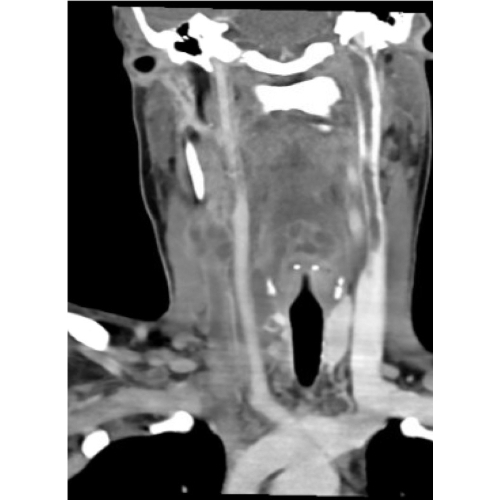

CT Soft Tissue Neck with IV Contrast revealed multi-locular fluid collections within the prevertebral space and along the right cervical lymph node chain with involvement of the right lobe of the thyroid and thyroid isthmus, an occlusive thrombus within the right internal jugular vein and nonocclusive thrombus on the left, and patchy airspace opacities at the lung apices.

Case Photo #1